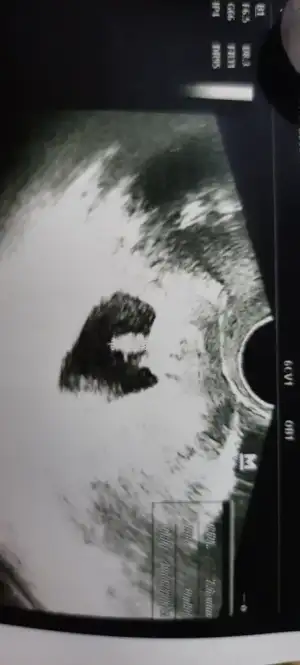

Muayene oldum kesesi oluşmuş şu an ikiz gibisinden bişey demediValla kese görmek için doktor gün veriyor genelde kese günü belki çıkar ikiz mi değil mi

Allah size bağışlasınMuayene oldum kesesi oluşmuş şu an ikiz gibisinden bişey demedi

Canım çok sevindimMuayene oldum kesesi oluşmuş şu an ikiz gibisinden bişey demedi